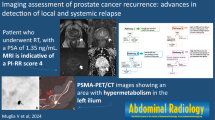

Detectable PSA >0.2 ng/mL following prostatectomy or rising PSA at least 2 ng/mL above the nadir following radiotherapy suggests residual or recurrent disease. Establishing the extent of disease in this setting is challenging, particularly when PSA remains relatively low.

mpMRI and supersensitive PET scans can help to determine the specific location of a local recurrence and/or whether there is distant disease.

Imaging with Ga-68 prostate-specific membrane antigen (PSMA) has thus far demonstrated the greatest sensitivity with respect to disease detection at low PSA values, with superior detection rates compared to choline-based PET [59] although it has not yet obtained FDA approval. Ga-68 PSMA targets a transmembrane protein overexpressed in prostate cancer cells by 100–1000-fold depending on grade and stage of disease [54].

This includes chest imaging, prostate MRI, and consideration of abdominopelvic CT or MRI or fluciclovine PET scan (Fig. 2.16).

Ultrasensitive PET scans are particularly helpful in localizing recurrent disease when MRI imaging findings are not definitive. Choline PET was found to have 95% sensitivity and 73% specificity for recurrence in the post-RT setting [70]. PET can also be invaluable for diagnosing metastatic disease in this setting, as noted in Sect. 2.5.1 and shown in Fig. 2.17.